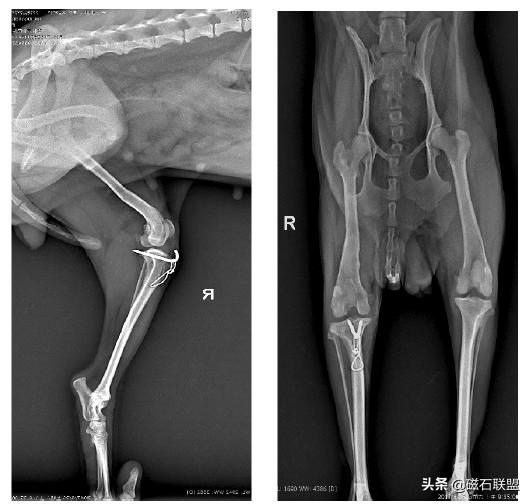

★影像学检查

通过X光线照射可以了解犬只的具体病情,是内侧还是外侧脱出,还可以了解脱出严重程度以各类信息,这是最有效也是最直接的诊断方法,可依此制定最终的确诊方案。

下面就将举一个髌骨脱位的病例来具体说明:

宠物名称:耀耀,品种:泰迪犬,性别:母,年龄:七岁,体重:3kg。

主述:几个月前从桌子上摔下后有单腿跳行的行为,最近发现后肢走路明显跛行,特此就医。

X射线检查:

泰迪犬后腿一瘸一拐的怎么回事,泰迪犬性格缺陷

影像学检查诊断为右后肢髌骨外脱位,与主人协商后决定进行手术。